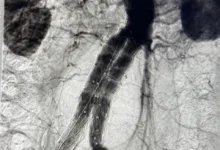

Ariel había sufrido la ruptura de un aneurisma cerebral y, tras la realización de una tomografía y múltiples pruebas clínicas, le informaron que su cerebro ya no funcionaba, pues estaba con muerte encefálica.